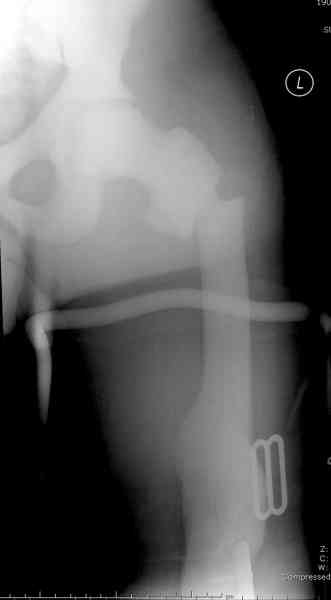

Что-то пациенту как-то не везет по жизни... Тоже самое - интрамедуллярный остеосинтез коротким штифтом для проксимального отдела бедра. Ранняя нагрузка сразу...

Наша тактика была бы - вертельный гамма стержень. Его длина 180 мм, должен поместиться до пластинки. Инструмент для формирования (не рассвреливания!) кнала, если он запаян, у нас есть.

Любой стандартный штифт для проксимального отдела бедра пройдет. TGN действительно из всех самый короткий, и поэтому предпочтительнее.